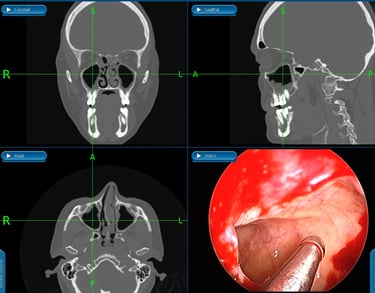

A dra Cynthia avalia em consulta médica, relacionando o desvio aos sintomas. Pois apenas a presença de um desvio de septo não significa que seja necessário operar. É fundamental estabelecer a relação dele com o causa dos sintomas: obstrução nasal, cefaléia, ronco, sinusite de repetição.

Pode ser necessário tomografia de nariz ou video naso fibroscopia

A septoplastia é realizada com anestesia e técnica minimamente invasiva. O objetivo é melhorar a respiração, preservar estruturas importantes e garantir um pós-operatório mais tranquilo. Na maioria das vezes pode ser realizada sob visão endoscópica e quando há necessidade de redução dos cornetos nasais, é realizada a turbinectomia por radiofrequência, técnica mais segura que permite recuperação mais confortável.